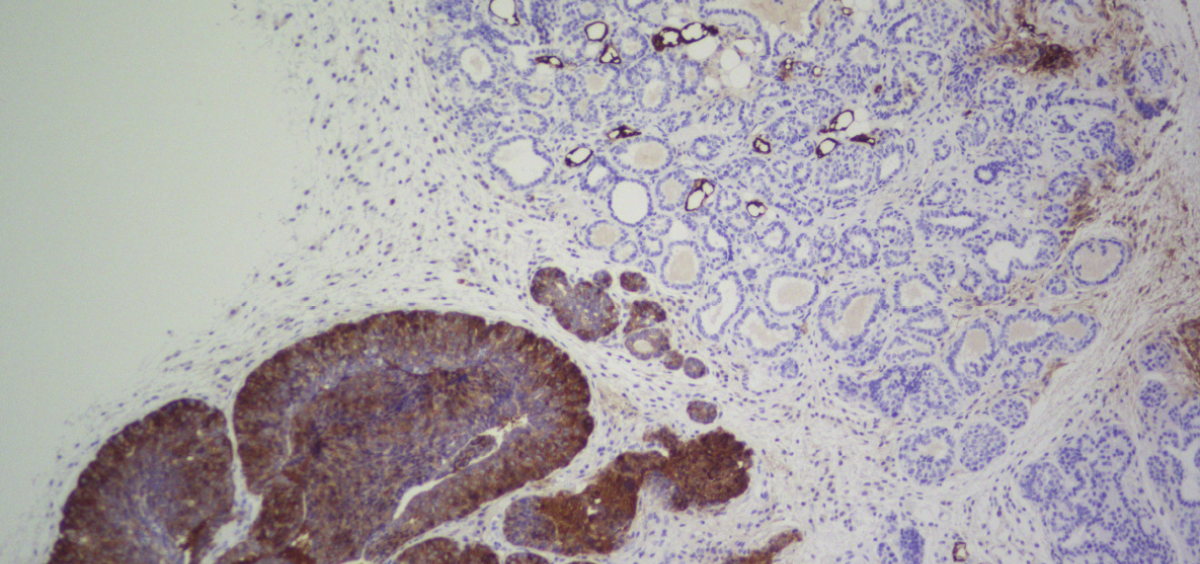

Se sabe que FASN está sobreexpresada en muchos tipos de cáncer, como el de próstata, de mama, de tiroides, colorrectal, de vejiga, de pulmón y de páncreas. Por este motivo, y aunque todavía no se conoce bien su relación con la enfermedad, científicos de todo el mundo la estudian como potencial diana contra el cáncer.

Un equipo de investigadores liderados por Miguel Ángel Quintela, jefe de Investigación Clínica del Cáncer de Mama del Centro Nacional de Investigaciones Oncológicas (CNIO), ha descubierto la conexión de esta enzima con el cáncer, y ha demostrado que las terapias que inhiben FASN son altamente eficaces contra el desarrollo de los tumores en su fase de formación, pero no para tratarlo cuando ya ha aparecido. Estos experimentos se han realizado en ratones y cultivos celulares.

Trabajando con un modelo transgénico de ratón que desarrolla un tipo agresivo de cáncer de mama, el equipo comprobó que al eliminar FASN los tumores no aparecían.